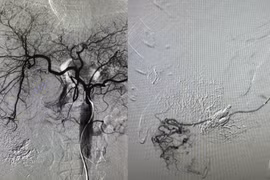

Nút mạch u gan và đốt sóng cao tần (RFA) trong điều trị ung thư gan đã giúp bệnh nhân ung thư tránh được những ca phẫu thuật mổ mở, rút ngắn thời gian hồi phục.

Nút mạch cầm máu trong điều trị u gan vỡ là giải pháp tối ưu cứu sống người bệnh bởi ưu điểm ít xâm lấn, bảo tồn gan, ít biến chứng, giảm tỷ lệ tử vong.